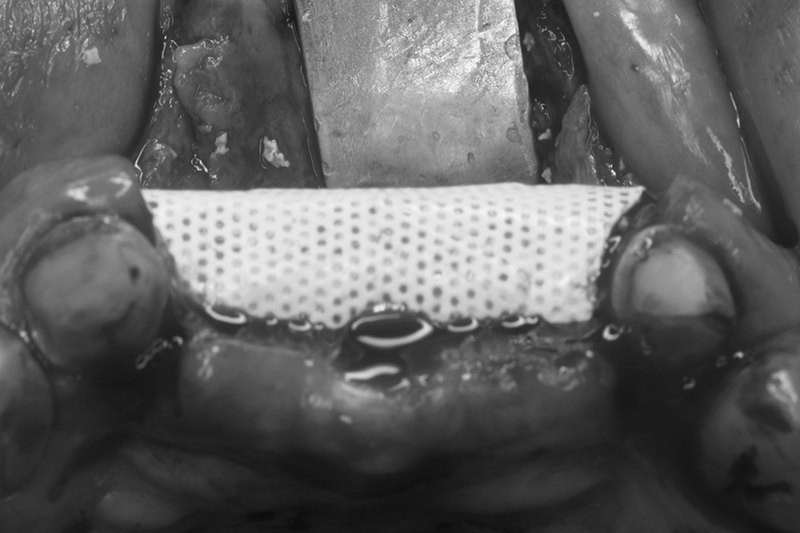

不可吸收再生膜Cytoplast

修剪合適範圍,並在舌側固定

迷你骨釘Tack固定再生膜及骨粉

迷你骨釘固定再生膜及骨粉